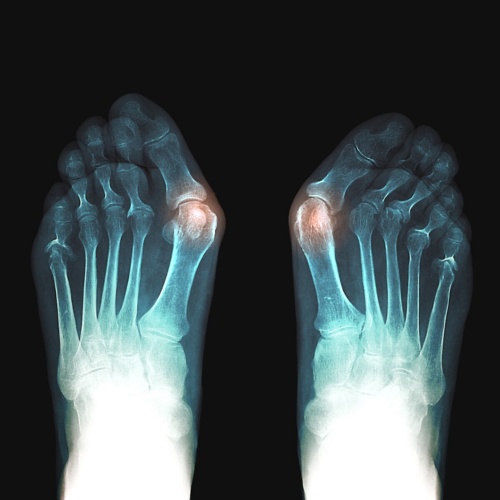

무지외반증(Hallux valgus)은 엄지발가락이 둘째 발가락 쪽으로 심하게 휘어지면서 엄지발가락과 관절을 이루는 첫 번째 중족골이 안쪽으로 치우쳐지는 변형을 의미합니다. 이로 인해 발 앞쪽이 넓어지거나 더 튀어나오게 되어 통증과 미용적 문제를 초래할 수 있습니다. 무지외반증은 주로 여성에게 발생하며, 젊은 연령대에서도 흔히 볼 수 있습니다. 초기 증상은 발의 형태 변화와 함께 발가락의 통증이 동반됩니다. 심한 경우에는 보행에도 영향을 줄 수 있습니다.

- X-선 검사 : 발의 구조를 확인하기 위해 X-선을 촬영하여 변형 정도를 평가합니다.